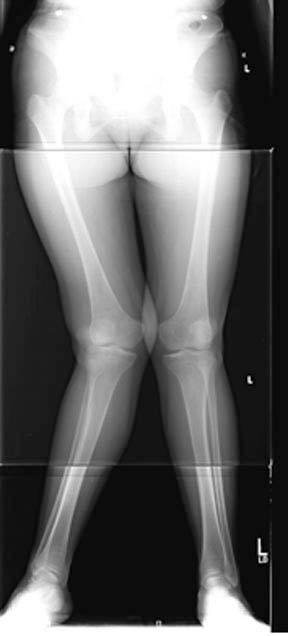

The following case describes a 20 year old female with knee pain and a severe knock-knee deformity (genu valgum) of both of her knees. She had not responded to physical therapy or medications.

1. This long casette radiograph demonstrates the severe deformity in her femurs that is causing the knock-knee deformity. She elected to undergo a correctional osteotomy of the femur in order to help her pain as well as to decrease the chance of progression of arthritis in the outer part of her knee. The contours of the femur are traced on paper and the correction of the deformity is planned.